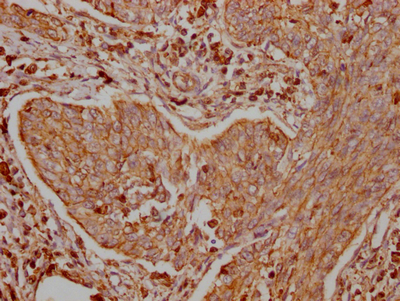

IHC image of CSB-RA786226A0HU diluted at 1:100 and staining in paraffin-embedded human cervical cancer performed on a Leica BondTM system. After dewaxing and hydration, antigen retrieval was mediated by high pressure in a citrate buffer (pH 6.0). Section was blocked with 10% normal goat serum 30min at RT. Then primary antibody (1% BSA) was incubated at 4℃ overnight. The primary is detected by a Goat anti-rabbit IgG polymer labeled by HRP and visualized using 0.05% DAB.